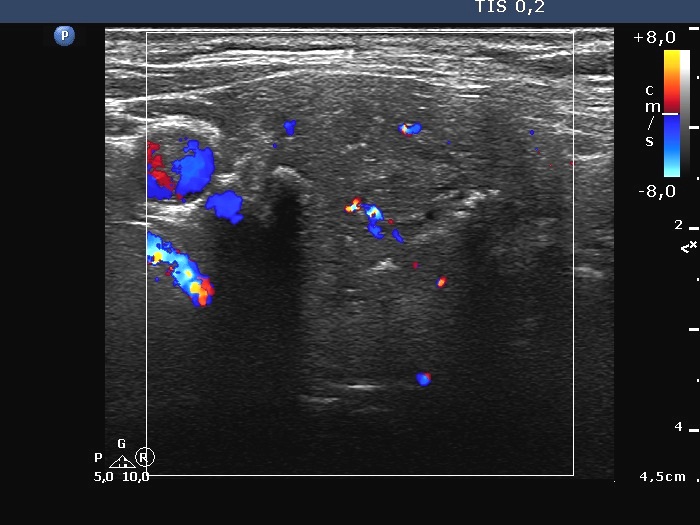

Ultrasonography. The thyroid was echonormal. A large hypoechoic nodule occupied almost the entire right lobe. The nodule showed various intranodular echogenic figures, including microcalcifications, macrocalcification and non-specific figures. The borders were indistinctive. The lesion was suspicious spreading extrathyroidal.